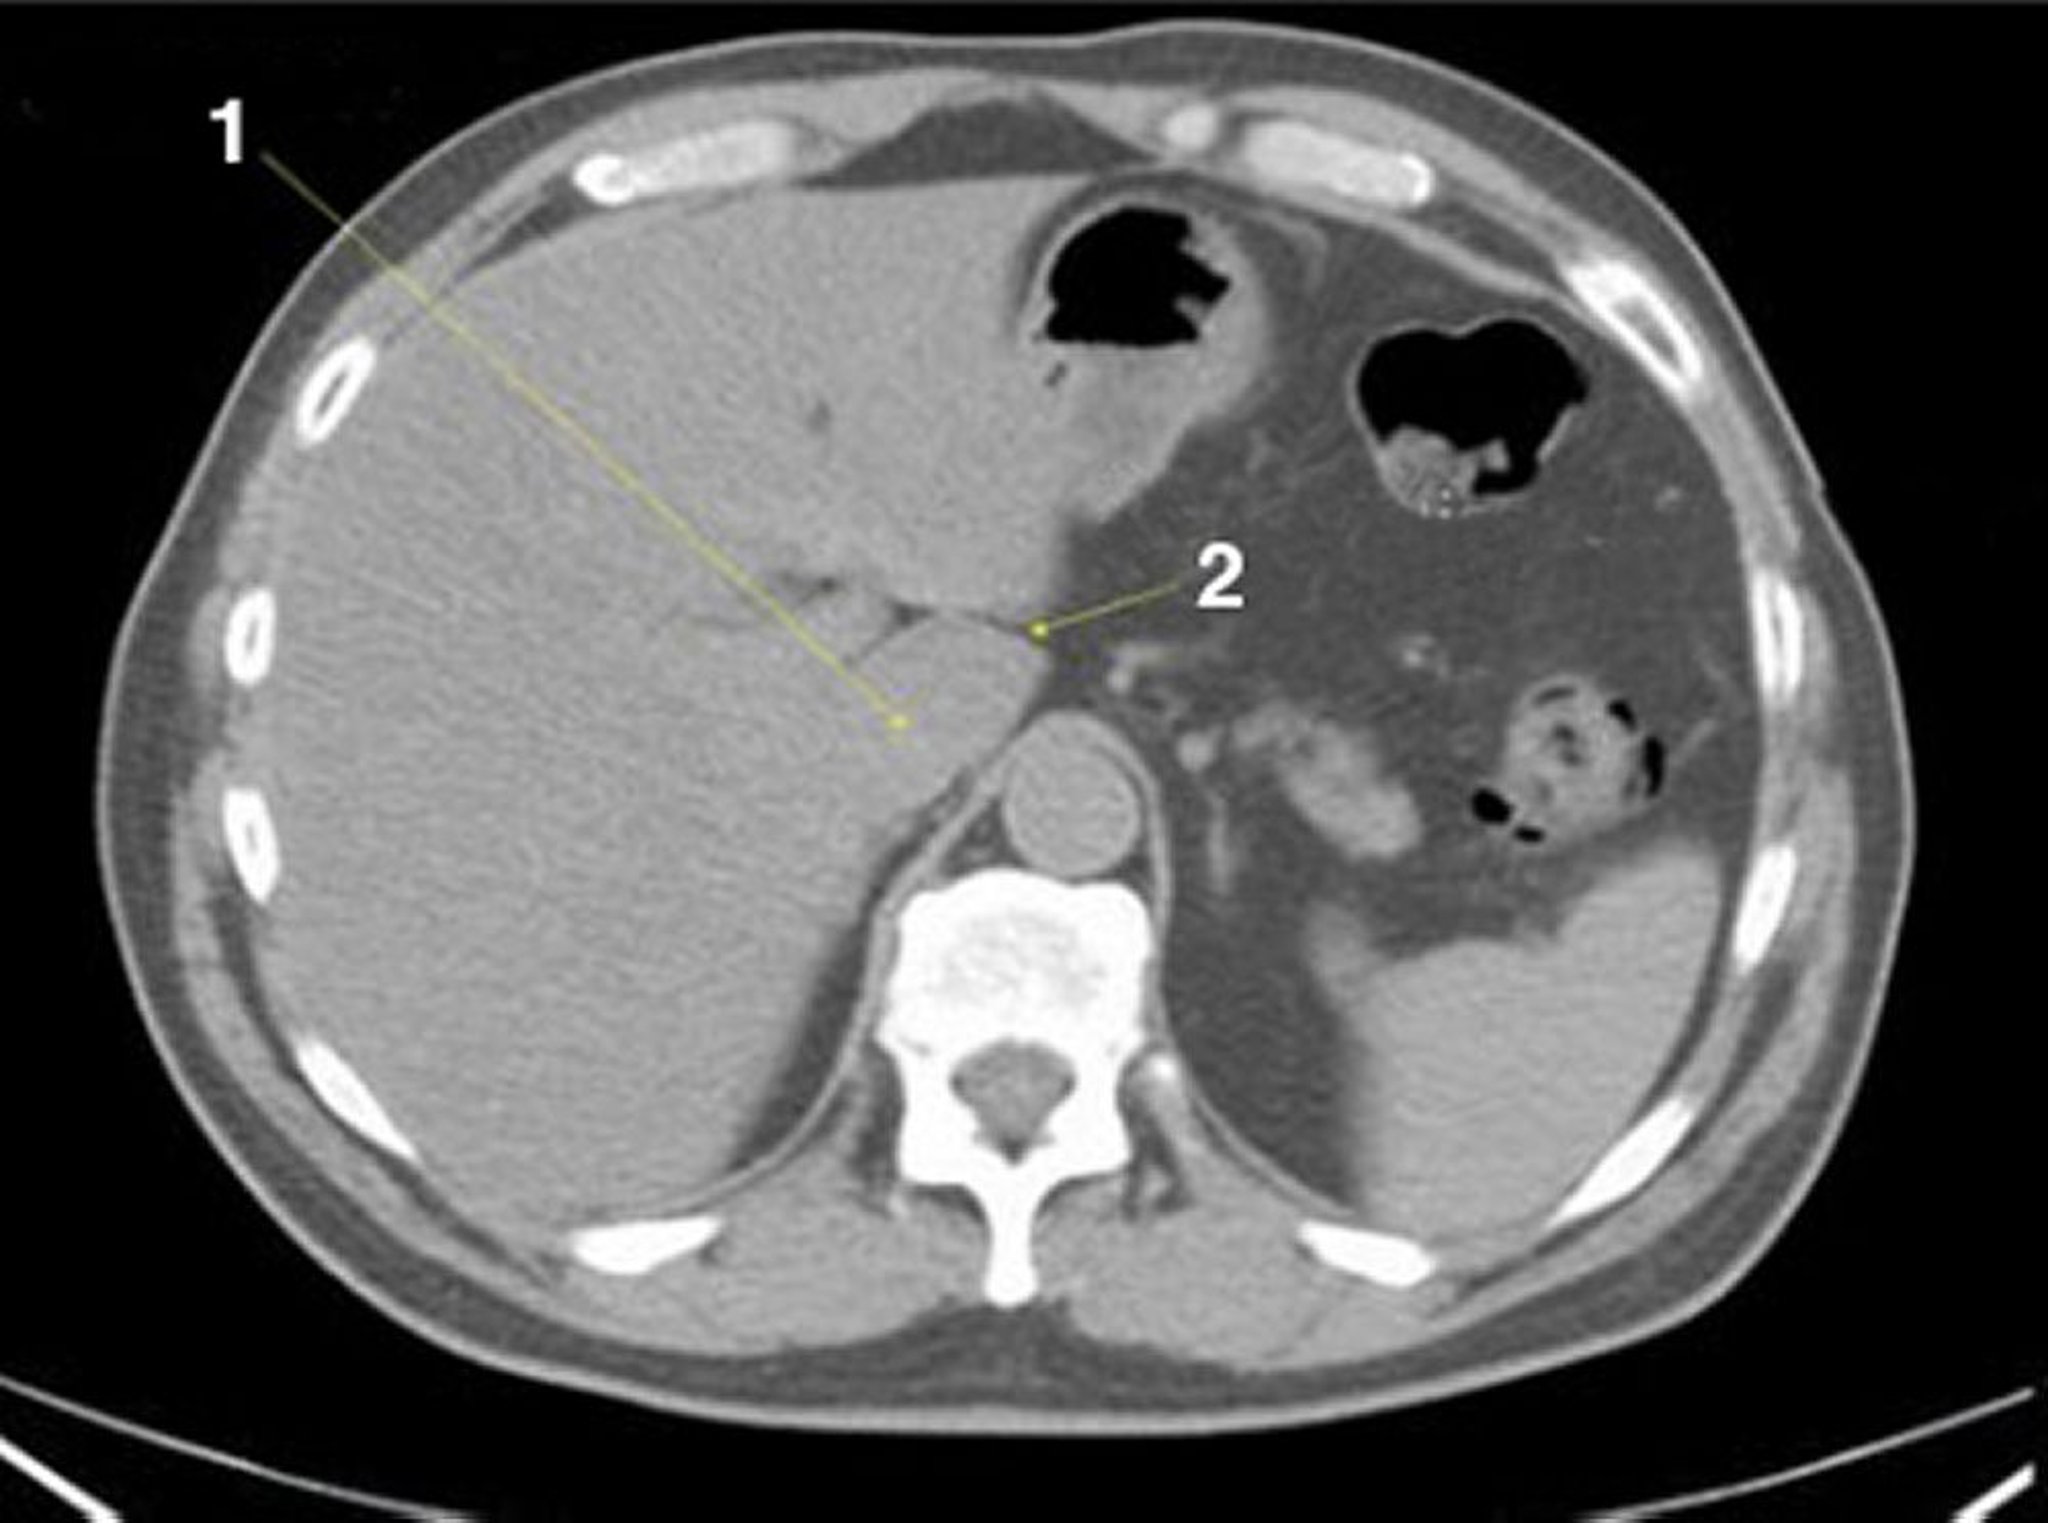

TC senza contrasto dell'addome e della pelvi che mostra un'anatomia normale (Slide 4)

1 = lobo caudato del fegato; 2 = fessura per il ligamentum venosum.